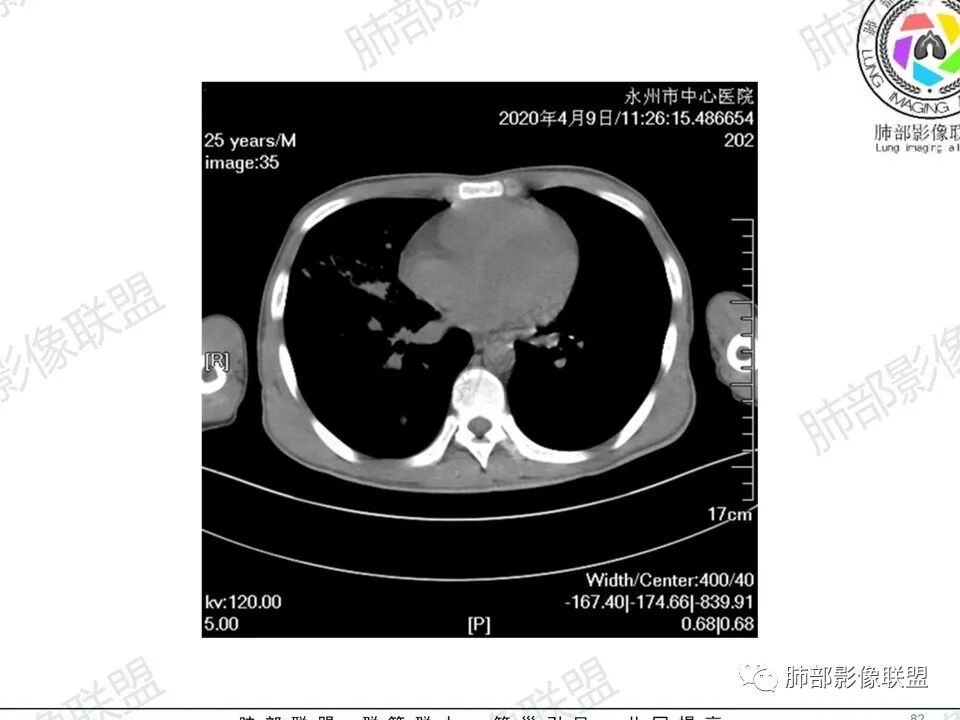

3、影像表现:双肺散在斑片影及结节影,部分结节内可见血管穿行,斑片影沿支气管血管束分布,近胸膜侧病变收缩不明显。部分中央淋巴间质增厚,小叶间隔增厚。病灶内支气管穿行,部分支气管略扩张。局部小结节呈串珠样改变。纵隔、肺门区、锁骨上及腋窝淋淋巴结肿大,部分有融合。心腔低密度。脾大。

5.双肺门及纵隔淋巴结显著增大,这改变相当显眼。这里强调“双肺门”及“多发”!

增大的淋巴结密度偏低且均匀。此外患者有体表淋巴结增大。

7.脾脏增大。

1.临床表现明显,纵隔及双肺门淋巴结显著肿大,临床最为担心的还是淋巴瘤!

尤其患者有贫血及脾脏增大,又有体表淋巴结增大时,这也是临床相对常见的情形。

2.右肺多发微小结节影,部分沿血管束分布,尽管未见小叶间隔改变,但双肺门淋巴结增大确实应当首先排除结节病,但经验上说,结节病的增大淋巴结密度往往较高、较密实,边界往往清楚,“独立性”很强,绝无“融合之嫌”!此外,较少出现贫血、脾大,临床表现也往往较轻微。